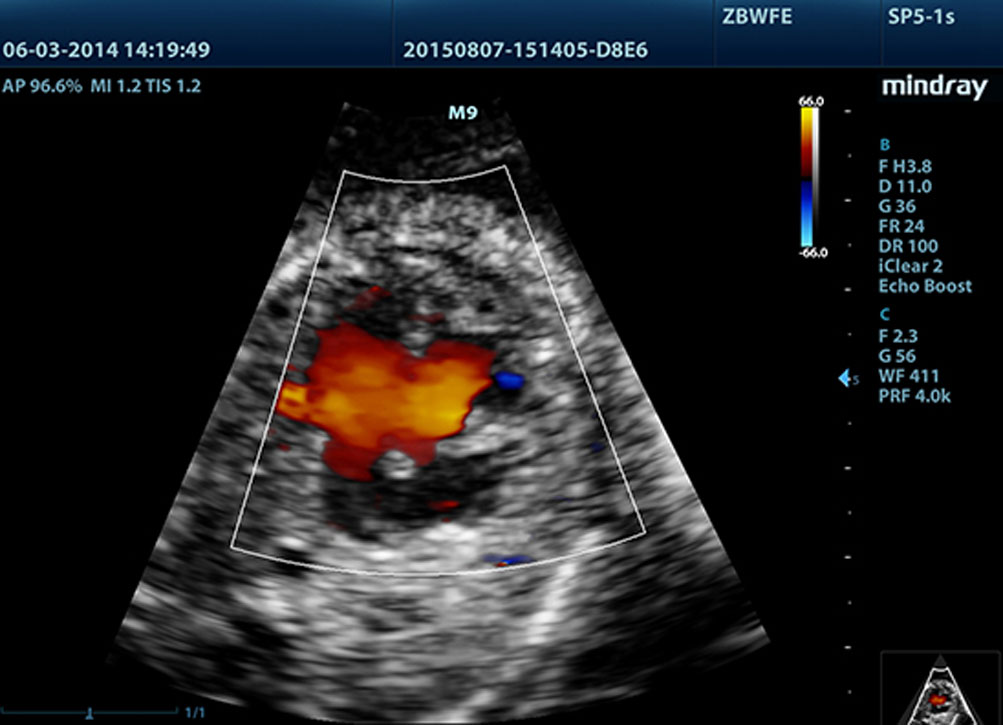

?? ?????? ?? LVO

M9? ???? ??? ?? ?? LV ????? ?? ?? ??? ?? ? ?? ??? ???? ??? ??? ?? ?? ???? ?????. M9? ?? ????? ??? ???? ??? ?? ?? ??? ?? ??? ???? ?????. ? ???? ???? ??? ?? ???? ? ?? ??? ?? ?? ???? ?? ?????.

??? ??(TSI)

??? ??? ?? ?? ??? ??? ?? ?? ??? ??????. ??, ??, ??, ??? ??? ? ?? ?? ??? ??? ? ????.